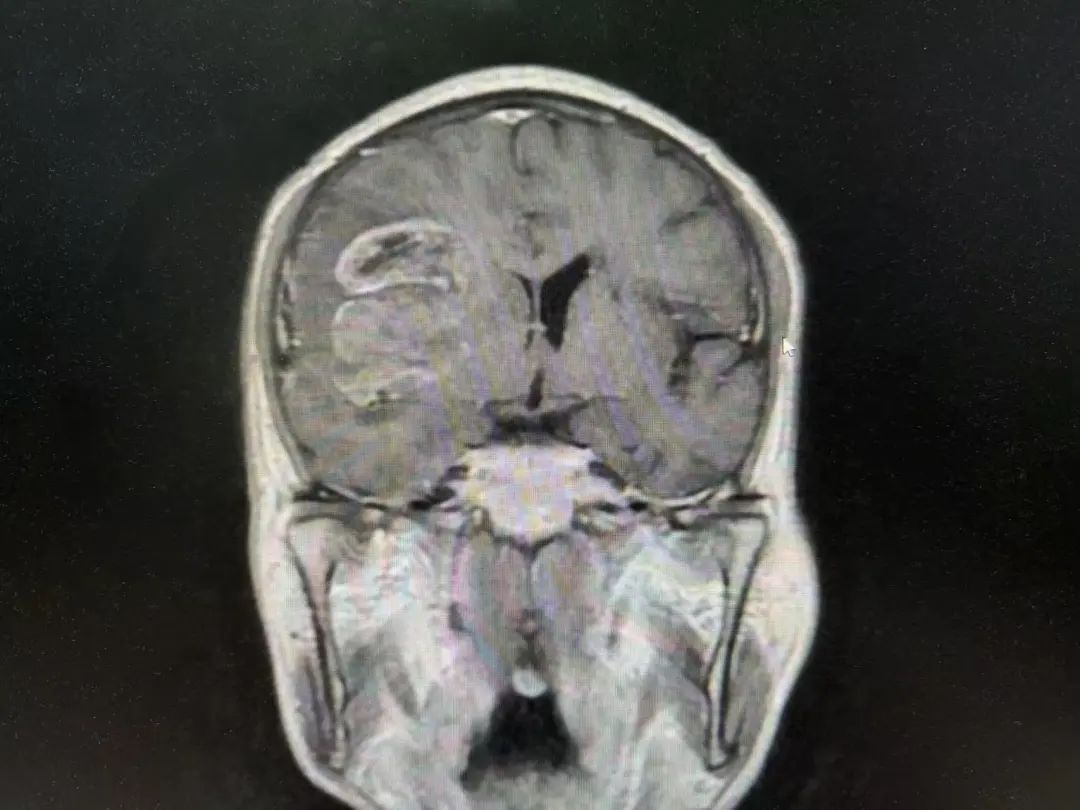

男性 | 67歲

主訴:左側(cè)口角流涎10天,左側(cè)肢體無力7天。

MR:右側(cè)大腦半球腫瘤性病變,考慮高級別膠質(zhì)瘤(大者大小約3.8cmx4.6cmx3.4cm)。